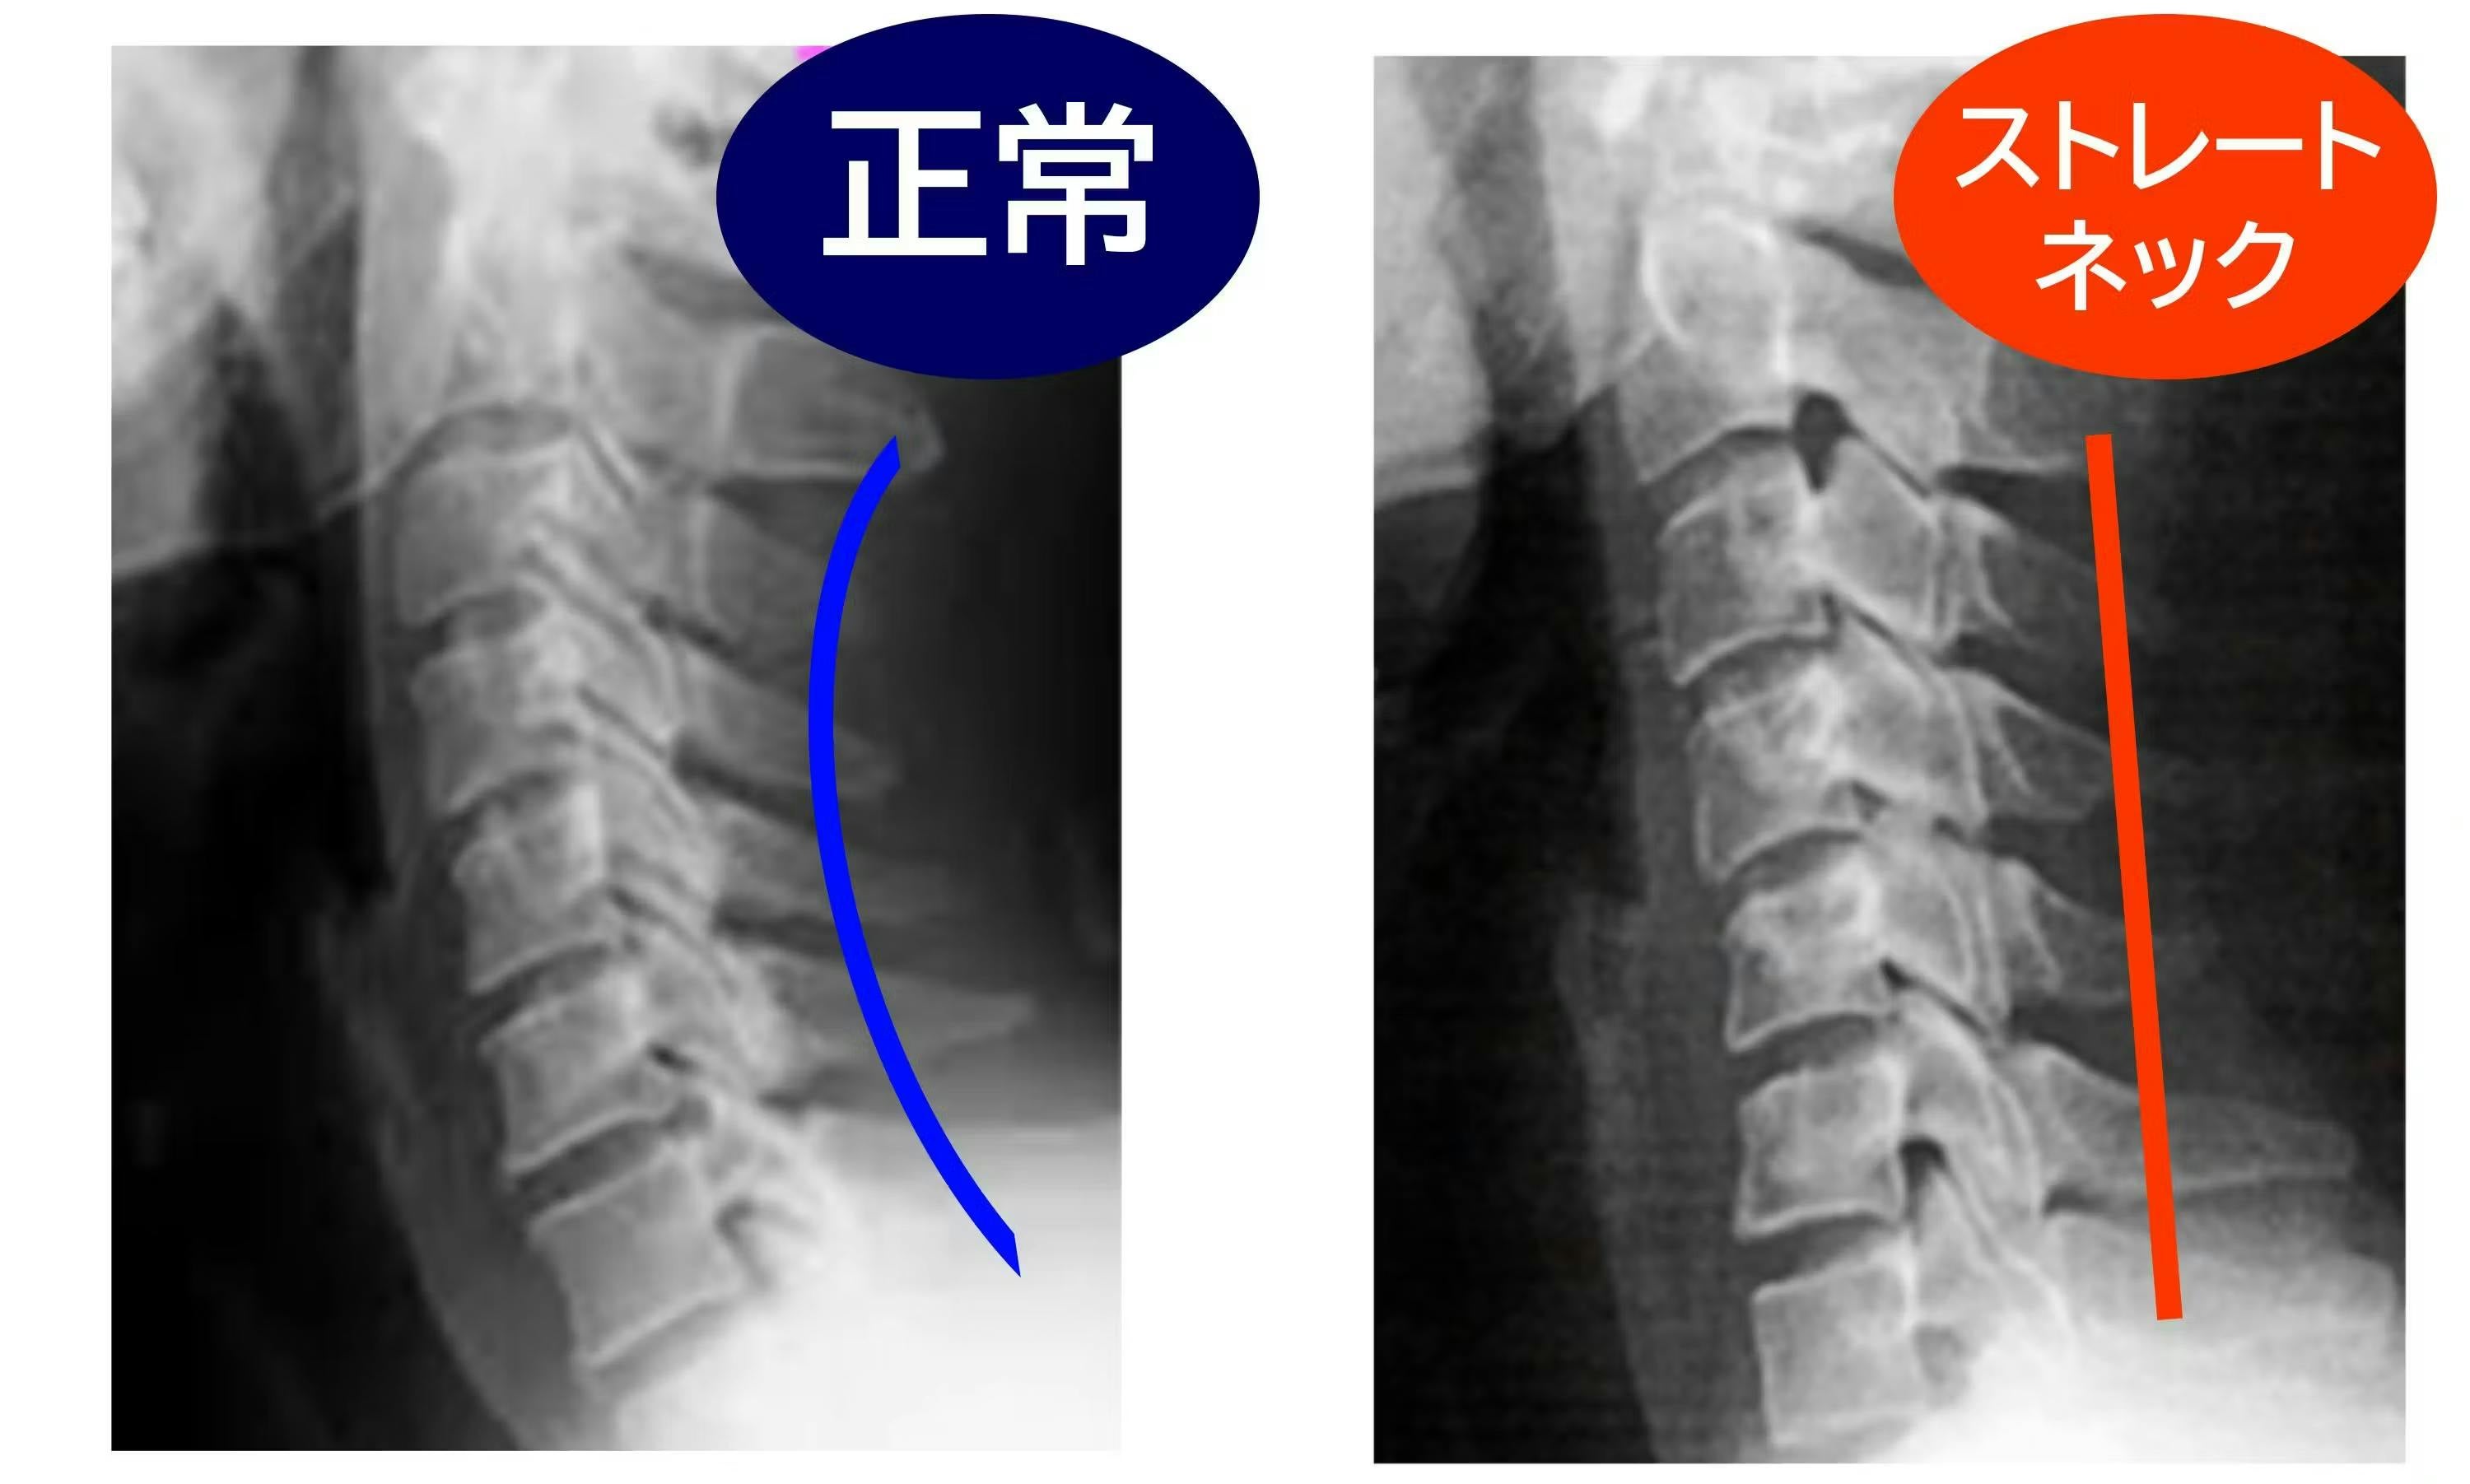

小さな画面の小さな文字や動画を追っているうちに、気づけば前かがみの姿勢をずっと続けていたということ、きっと誰でも経験があると思います。

Q:首に異常がある場合でも使えますか?

A:頸椎ヘルニアや重度の首の疾患をお持ちの方、医師の治療を受けている方は、ご使用前に必ず医師にご相談ください。